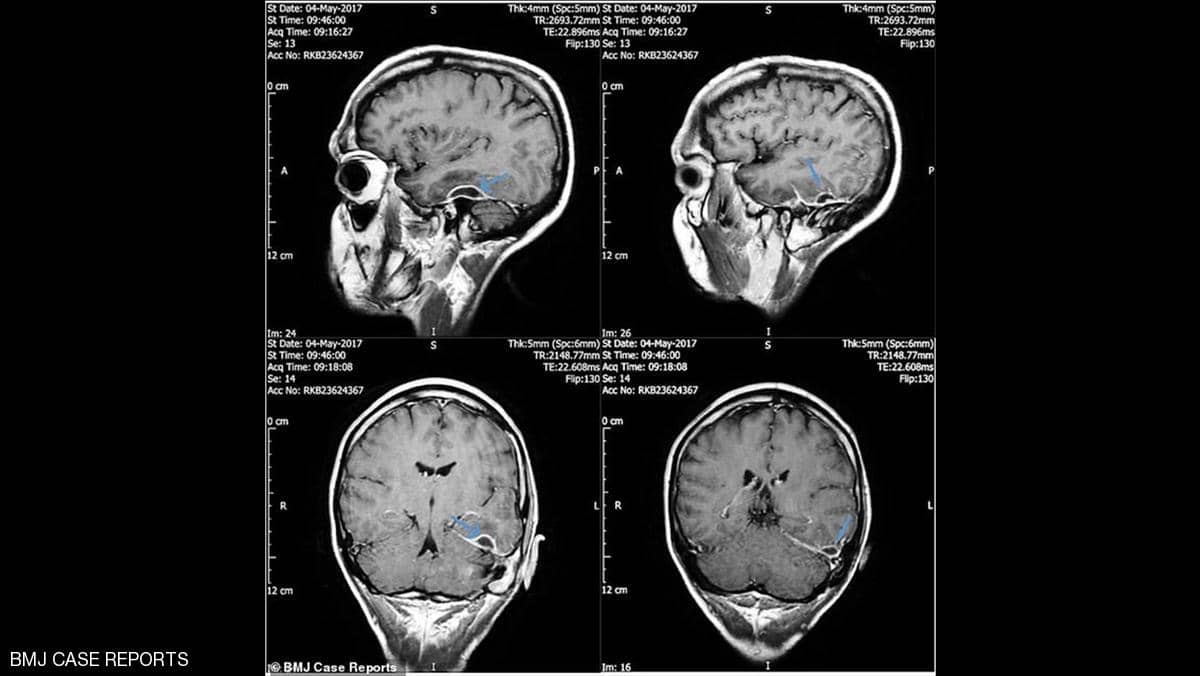

فقد نقل رجل إلى المستشفى على عجل بعد انهياره، ليكتشف الأطباء أنه مصاب بعدوى في جمجمته تسببت بها قطعة قطن علقت في أذنه، بحسب صحيفة "ميل أونلاين" البريطانية.

ففي المستشفى، اكتشف الأطباء أن المشكلة "باتت" أعمق مما كان يعتقد وأنها توجد داخل جمجمته.

وعندها تبين لهم أن قنوات الأذن عنده مصابة بالتهاب حاد مع وجود "أوساخ عالقة" سببتها قطعة قطن.

وبحسب الأطباء فإن الالتهاب أصاب الخلايا داخل الجمجمة، ولم يصل إلى خلايا الدماغ.